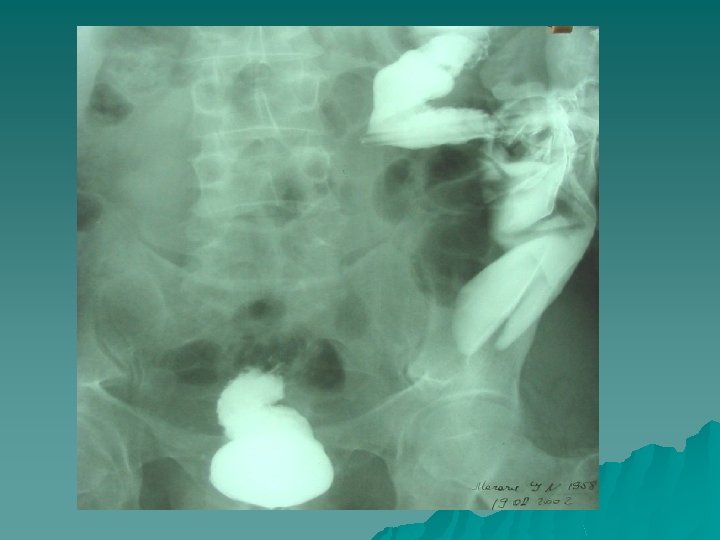

Metodele radiologice : 1. Pasaj cu bariu 2. Irigoscopia 3. Fistulografia 4. Fistulografie selectivă 5. Fistulografie cu intubare endoscopică.

FISTULOGRAFIA UNUI PACIENT CU O FISTULĂ POSTOPERATORIE

Proctografia şi fistulografia la un pacient cu descendostoma terminală